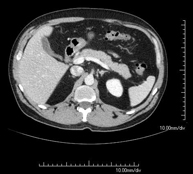

- Abdominal and pelvic CT

Diagnostic test that consists of obtaining high-definition anatomical images (bone structures, vascular structures, liver, pancreas, gallbladder, kidneys, adrenal glands, spleen, small and large intestine, bladder, uterus and ovaries, prostate and seminal vesicles, ureters, etc.) using CT (computed tomography) equipment. Most studies require the use of iodinated contrast.

- Kidney CT

Diagnostic test that involves obtaining high-definition anatomical two- and three-dimensional images of the kidney and urinary system using CT (computed tomography) equipment. The study is performed before and after the use of iodinated contrast in different ‘renal phases’ for functional and anatomical assessment (renal parenchyma, ureters, urinary bladder, renal arteries and veins, etc.), as well as adjacent structures (inferior vena cava, abdominal aorta, liver, spleen, etc.). It is particularly recommended when kidney damage is suspected, in patients with blood in their urine or haematuria, etc.

- Abdominal aorta CT angiography

A non-invasive diagnostic test that involves studying the abdominal aorta by obtaining high-definition anatomical images using CT (computed tomography) equipment and iodinated contrast. With the aid of workstations specialised for arterial studies, the image quality supports 2D and 3D reconstructions. It is indicated in patients with vascular disease (atherosclerosis), aortic aneurysms, abdominal pain of possible vascular origin, pre-surgical studies of lesions adjacent to the abdominal aorta as a vascular ‘map’, etc. Information obtained non-invasively is indispensable for patients requiring percutaneous or surgical processing. In patients who only require tracking of vascular lesions, this technique is the non-invasive technique of choice, together with MRI angiography.

- Renal artery CT angiography

A non-invasive diagnostic test that involves studying the renal arteries by obtaining high-definition anatomical images using CT (computed tomography) equipment and iodinated contrast. With the aid of workstations specialised for arterial studies, the image quality supports 2D and 3D reconstructions. This test is recommended, for example, in patients suffering from refractory hypertension that does not respond to processing, in patients with kidney damage in order to obtain a pre-surgical ‘vascular’ map, etc.